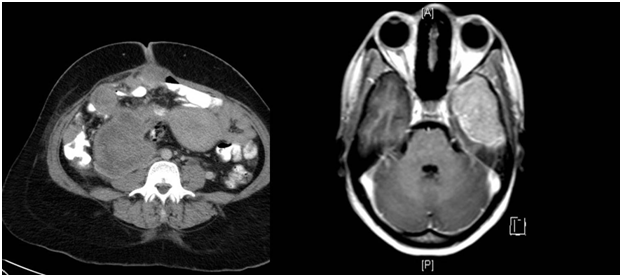

Figure 2 Contrast enhanced T1 weighted images, MRI of the brain showing an intensely enhancing mass in the left middle cranial fossa.

Figure 3 Contrast enhanced CT axial sections of the abdomen showing a large heterogeneous mass arising from the pancreatic tail.

Figure 4 T2 weighted coronal sections of the pelvis showing a heterogeneous mass in the scrotum.